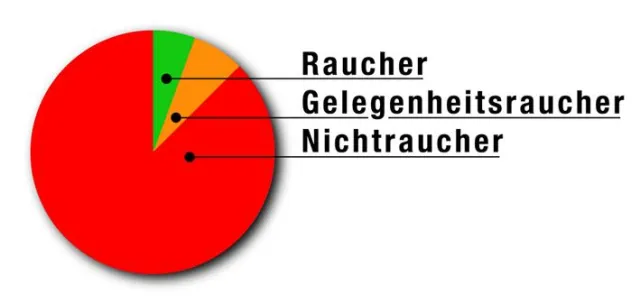

Rauchen ist nicht nur schädlich

Einer Umfrage zufolge leiden 15 mal mehr Nichtraucher unter Aphthen als Raucher.

In einer Onlineumfrage unter 303 Betroffenen gaben 87,5% an Nichtraucher zu sein. 5,5% waren Raucher, weitere 7,0% bezeichneten sich als Gelegenheitsraucher.